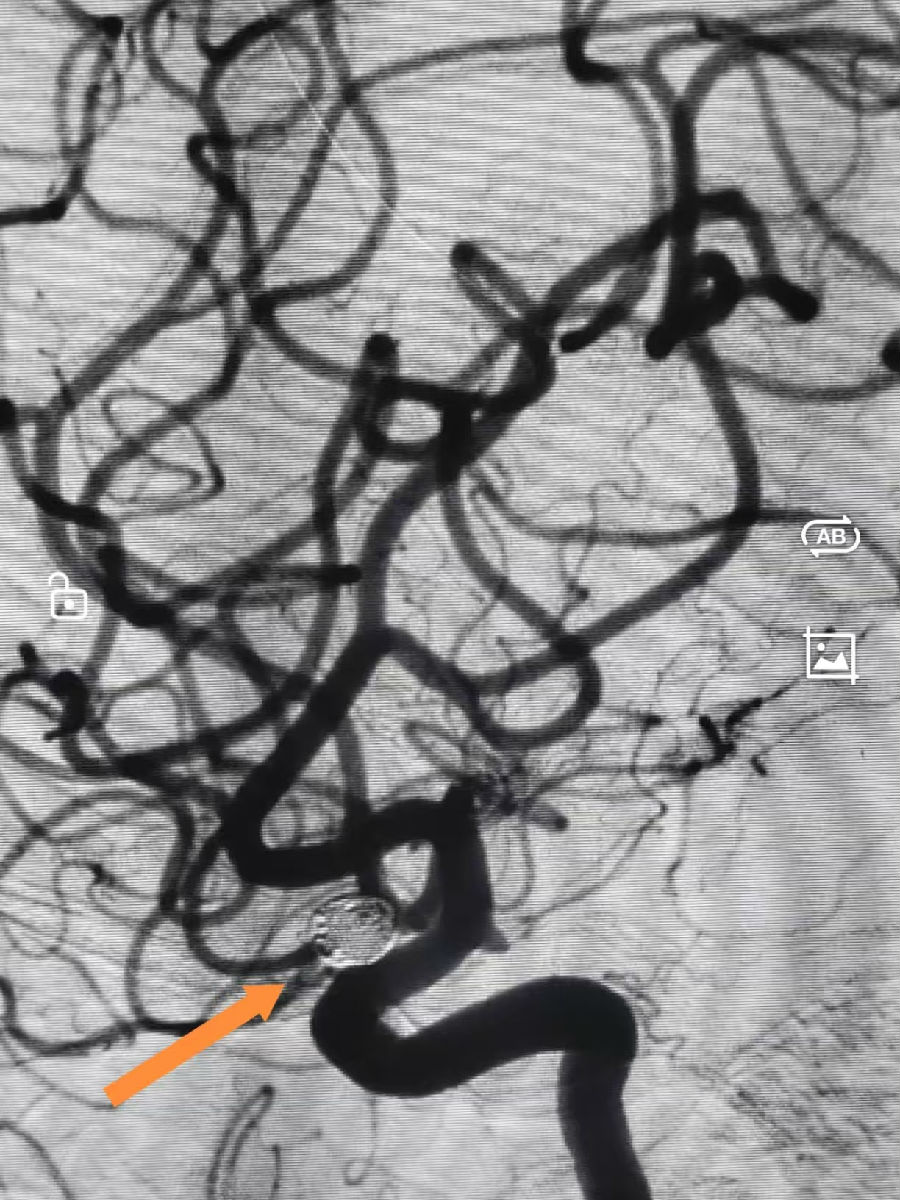

患者为51岁男性,因“突发头晕、行走不稳2小时”急诊入院。头颅MR检查提示:多发腔隙性脑梗死,且前交通动脉存在瘤样突起,高度怀疑动脉瘤。进一步行全脑血管造影(DSA)后明确:前交通动脉处可见一大小约10mm×6mm的囊状动脉瘤,瘤颈约3mm,形态不规则,并伴有子囊形成,属于破裂出血的高风险类型。

“这就像在血管迷宫中穿针引线,每一步都需要毫米级的操控。”主刀医生白利刚副主任医师形象地解释道。随后,团队依次向瘤腔内填入10枚可解脱式弹簧圈,直至动脉瘤腔被致密填塞。即刻复查造影显示:动脉瘤完全不再显影,载瘤动脉---前交通动脉及邻近大脑前动脉血流通畅,未见血栓或血管痉挛等并发症。整个栓塞操作仅用时约20分钟,穿刺点仅有2毫米。